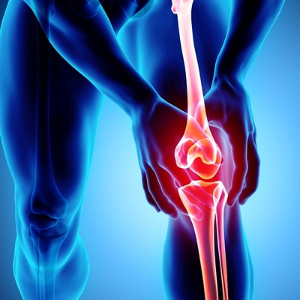

콘드로이친은 주로 관절을 둘러싼 연골을 구성하는 물질로, 젊었을때는 체내에서 잘 생성되지만 연령이 증가하면서 체내에서 합성하는 능력이 저하되어, 중년이 되면 몸에서 필요한 양의 5% 밖에 생성되지 않는다고 합니다. 콘드로이친이 결핍되면 연골의 탄력이 떨어지고 닳을 수 있기 때문에 하루 1200mg의 섭취가 권장됩니다.콘드로이친 1200mg 효능

연구에 따르면 콘드로이친은 관절 건강에 상당한 효능을 보일 수 있다고 합니다. 콘드로이친 1200mg의 효능으로는 관절 통증을 줄이고, 관절 기능을 향상시키며, 골관절염의 진행을 늦추는 데 효과가 있다고 합니다.

콘드로이친 1200mg은 연골에 물을 끌어들여 충격 흡수 능력을 높이고, 이를 통해 관절 건강을 증진시킨다고 알려져 있습니다.